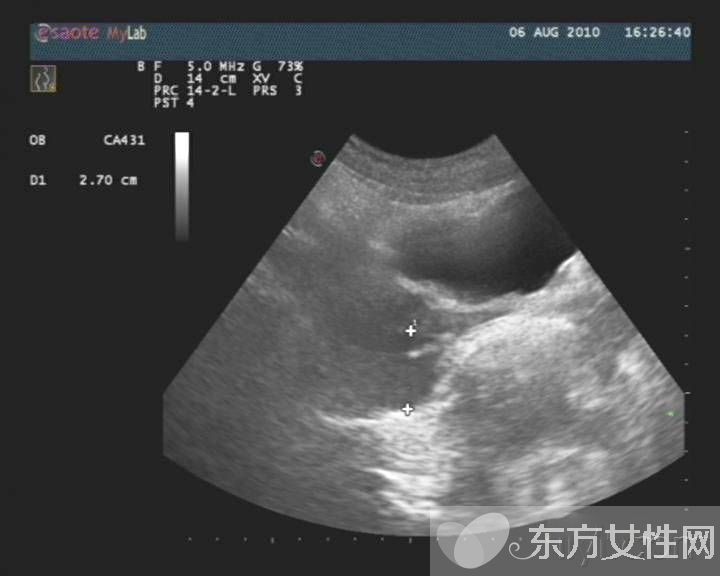

盆腔炎是指女性盆腔生殖器官、子宮周圍的結(jié)締組織及盆腔腹膜的炎癥,主要包括子宮內(nèi)膜炎、輸卵管炎、輸卵管卵巢膿腫、盆腔腹膜炎。

慢性盆腔炎常為急性盆腔炎未能徹底治療,或患者體質(zhì)較差,病程遷延所致。它可使機(jī)體發(fā)生慢性輸卵管炎與輸卵管積水、輸卵管卵巢炎及輸卵管卵巢囊腫、慢性盆腔結(jié)締組織炎。